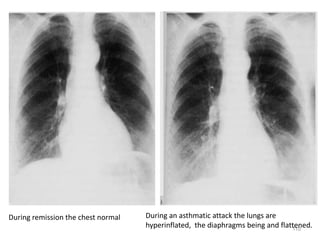

During remission the chest normal During an asthmatic attack the lungs are

hyperinflated, the diaphragms being and flattened.